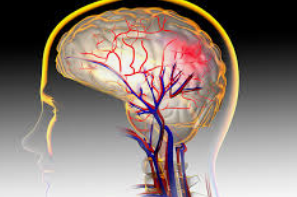

뇌동맥류는 발견 즉시 적절한 치료가 필요합니다. 특히 파열될 경우 뇌지주막하출혈과 같은 생명을 위협하는 상황을 초래할 수 있습니다. 파열된 동맥류는 갑작스러운 극심한 두통과 함께 심각한 신경학적 증상을 동반할 수 있어 신속한 의료 개입이 필수적입니다.

파열되지 않은 뇌동맥류는 대부분 무증상으로 발견되며, 우연한 검사에서 발견되는 경우가 많습니다. 그러나 동맥류가 커지면서 두통, 시력 저하, 복시 등의 증상이 나타날 수 있습니다. 파열된 경우에는 갑작스러운 극심한 두통, 구토, 의식 저하 등이 급격히 나타나며, 즉각적인 의료 조치가 필요합니다.